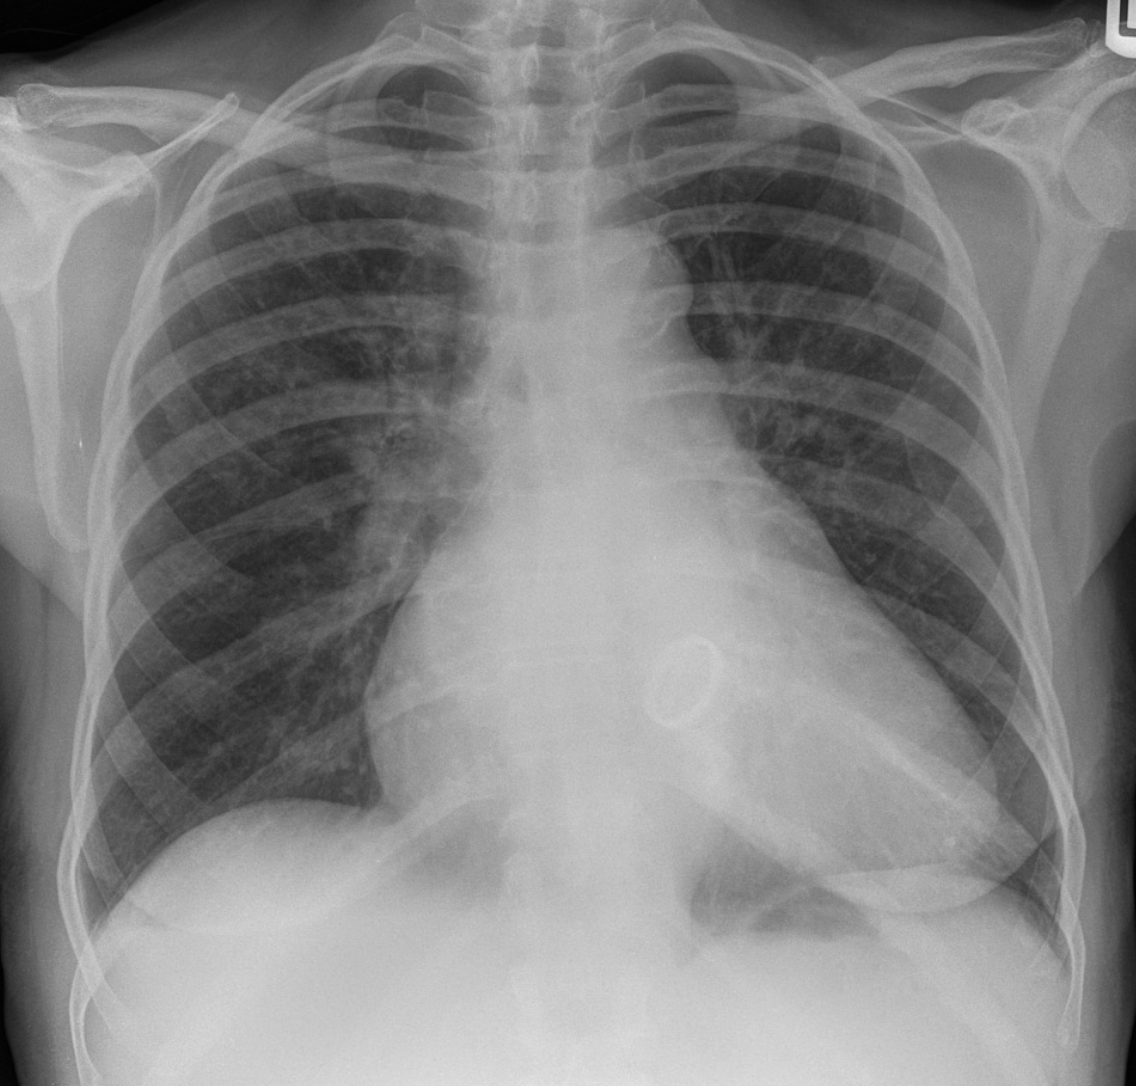

Pericardial effusion